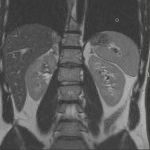

L’IRM abdominale est d’une grande utilité lorsqu’une analyse très fine des organes situés au sein de la cavité abdominale est nécessaire et que certaines lésions ne sont pas visibles avec les autres techniques d’imagerie (radiographie, échographie ou scanner).

Elle permet de réaliser des images en coupe ou acquisitions 3D apportant non seulement des informations sur l’anatomie de l’organe mais également sur la viabilité de certaines lésions et d’évaluer ainsi la réponse au traitement de façon plus précise.

Ce type d’exploration s’intéresse au foie, aux surrénales, aux reins, au pancréas, à la rate et au péritoine